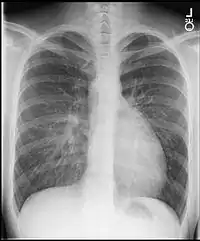

•Chest X-Ray: On chest X-ray (CXR), transposition of the great vessels typically shows a cardio-mediastinal silhouette appearing as an "egg on a string ", in which the enlarged heart represents an egg on its side and the narrowed, atrophic thymus of the superior mediastinum represents the string.[4]